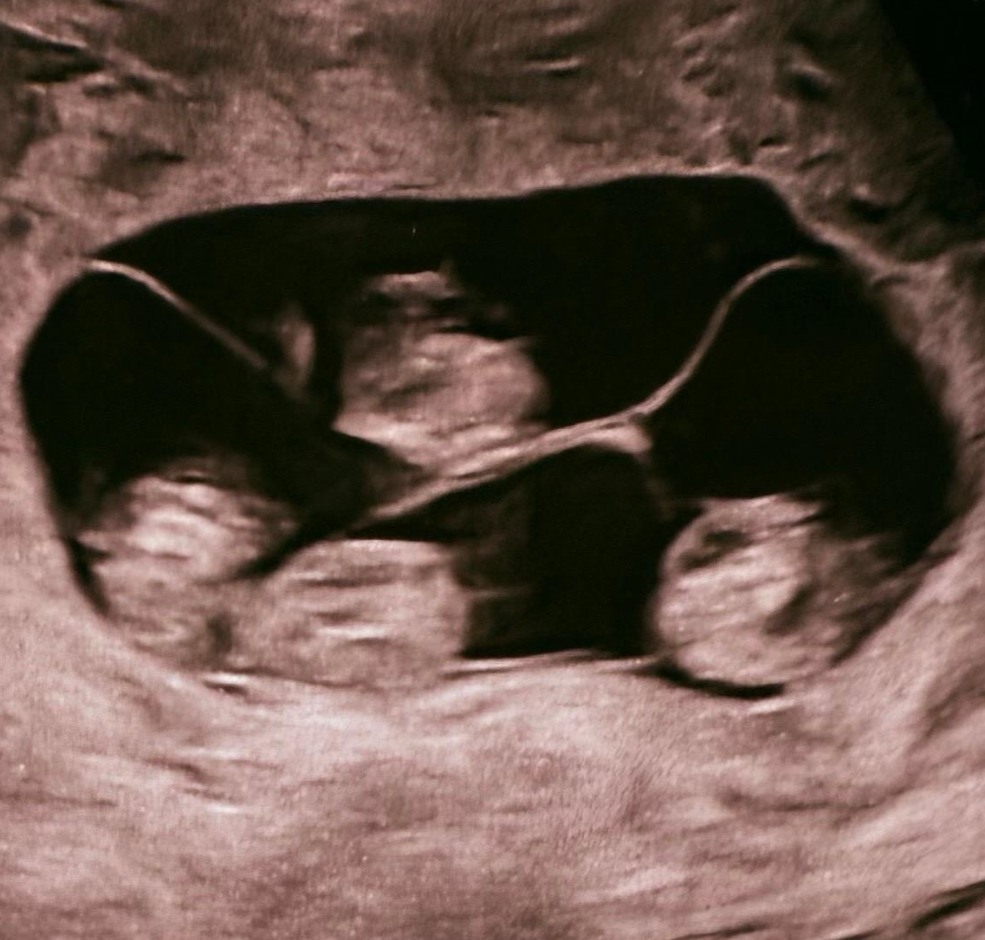

По словам заместителя главного врача родильного дома № 10 и профессора Евгения Михайлина, который также консультировал петербурженку, монохориальная — «однояйцевая» четверня — 1 случай на 15,5 миллиона родов. Вес новорожденных составил от 1360 до 1640 граммов, а рост — от 37 до 41 сантиметра. Для срока в 32 недели это очень хорошие показатели — говорят специалисты.

«В РФ не описано таких случаев! Получилось 32 недели, для четверни — это более чем прилично! Четверня — это очень круто! Удачи вам, ребята», — написал в личном блоге Евгений.

фото:соцсети